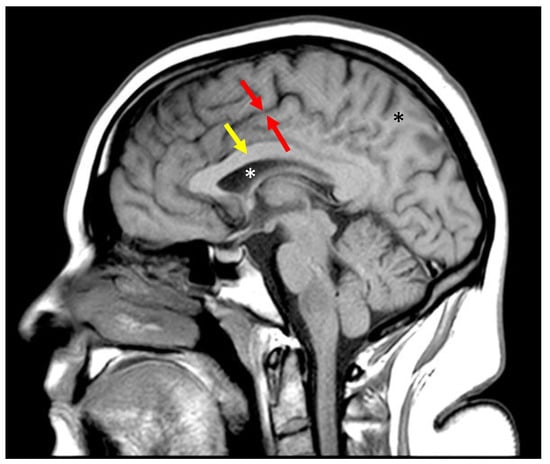

Figure 4.

Sagittal fast spin echo image of the brain with TR = 700 ms and TE = 10 ms. Gray matter (between the red arrows) is darker than the subcortical white matter (black asterix) and corpus callosum (yellow arrow). Fluid (white asterix) is even darker. This parallels the curve in Figure 2b.

Inversion recovery T1 filter. (a) T1 tissue property filter for the IR sequence with TI = 1100 ms and TR = 5000 ms. Tissues with T1 = 1594 ms are nulled by these parameters. The slope of the curve in the region of most tissues of interest is negative, so that an increase in T1 results in a decreased signal. This produces an image like an SE T1-weighted image. The slope of the left half of the filter is steeper than the slope of the plot in Figure 2b, resulting in increased contrast. (b) Sagittal fast spin echo image of the brain with TR = 5000 ms and TE = 1000 ms. Gray matter (between the red arrows) is darker than the subcortical white matter (black asterix) and corpus callosum (yellow arrow). Fluid (white asterix) is even darker. This parallels the curve in (a). There is increased contrast compared to Figure 4, which reflects the larger difference in signal between gray and white matter in (a) than in Figure 2b.